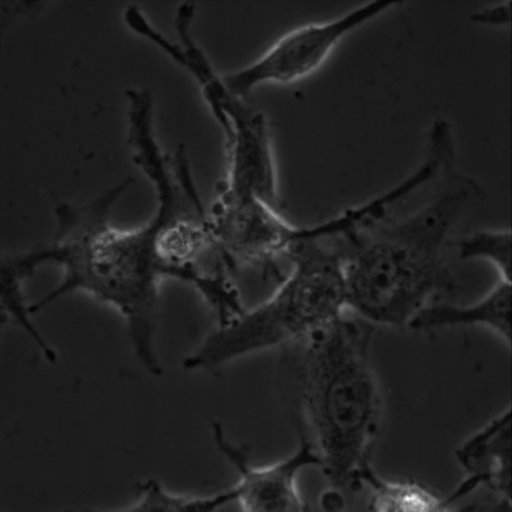

[ÇóÖú] Helaϸ°ûÅàÑøÎÊÌâ ÒÑÓÐ4È˲ÎÓë

ÅàÑøÒº£¨DMEM£ºFBS=9:1£©ÀïûÓмÓPS£¬ÖÖ°åÔ¼30 hºó¾ÍÊÇÕâÑùÁË£¬ÅàÑøÒºÈâÑÛ¹Û²ìÒ²ÊÇÇåÁÁ͸Ã÷µÄ£¬ÇóΪʲôϸ°û»á³¤µÃÏñÈöÁËÑεĺɰüµ°Ò»Ñù£¿£¿

Hela-3-40X-ph.jpg

¿ÉÄÜÊÇÖ§Ô­ÌåÎÛȾÁË¡£

Âò¸ökit¼ì²éÒ»ÏÂÊDz»ÊÇÖ§Ô­ÌåÎÛȾ£¬Èç¹û²»ÊÇ£¬ÄǾÍÊÇϸ°ûÀÏ»¯£¬ÈÓÁ˰ɡ¤¡¤¡¤¡¤

¿´×ÅÀàËÆÖ§Ô­Ìå¸ÐȾ¡£»¹ÊǼì²éһϰɡ£